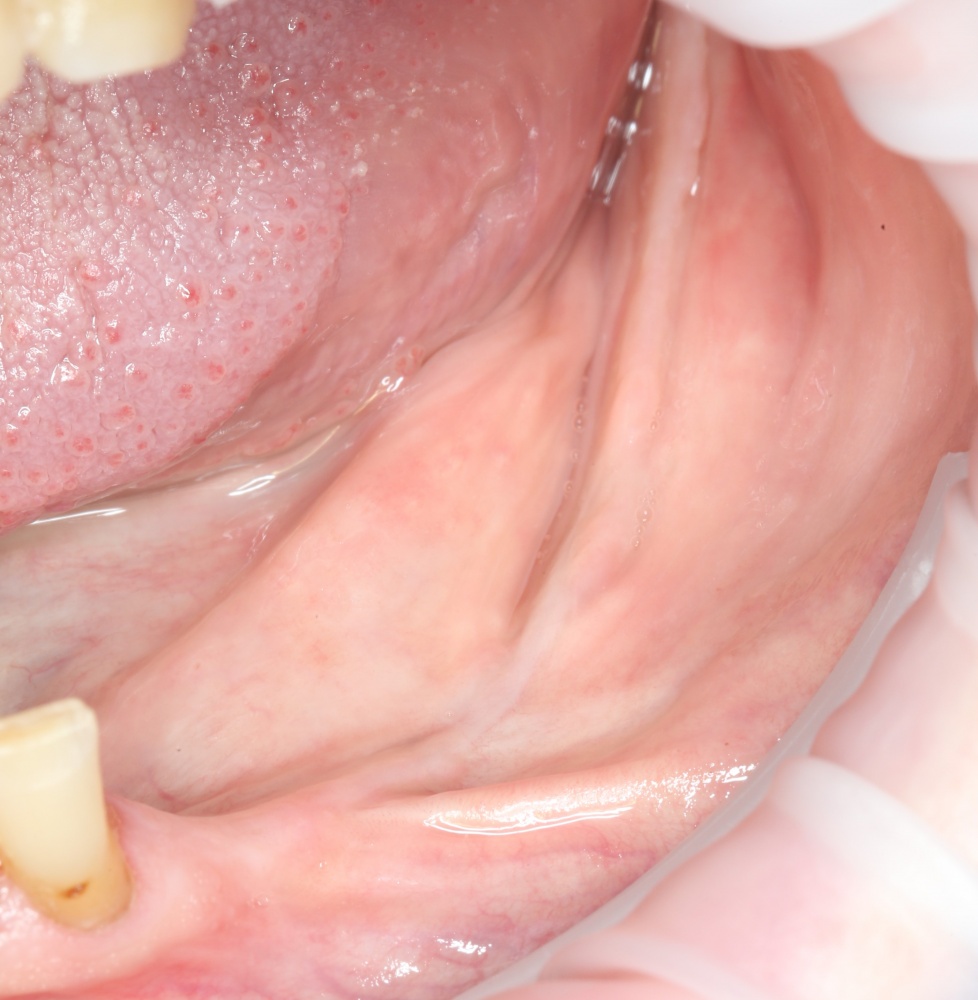

Но вот проблема — при длительном отсутствии зубов, травматичном удалении или из-за воспалительных процессов костная ткань альвеолярного отростка нижней челюсти атрофируется, меняет свою конфигурацию. Иногда довольно значительно:

A09A6305 (2) A09A6306 (2)

Можно ли в таких условиях поставить импланты? Скажу честно, можно. Но эти импланты будут короткими и тонкими, а находиться будут в таких положениях, в которых ортопеду будет очень сложно (иногда даже просто невозможно) их нормально протезировать.